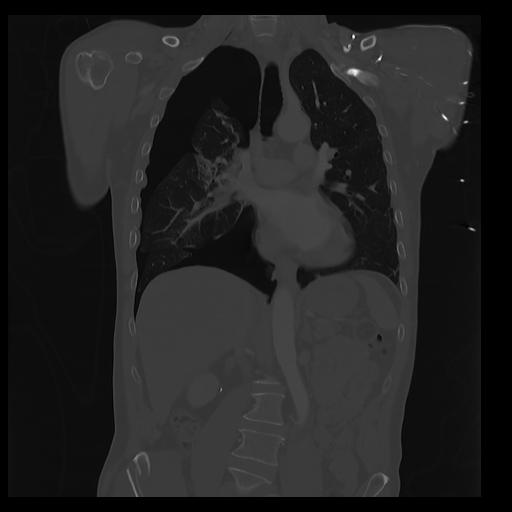

32 PULMON,CE,Coronal,3.000,PULMON,Coronal,